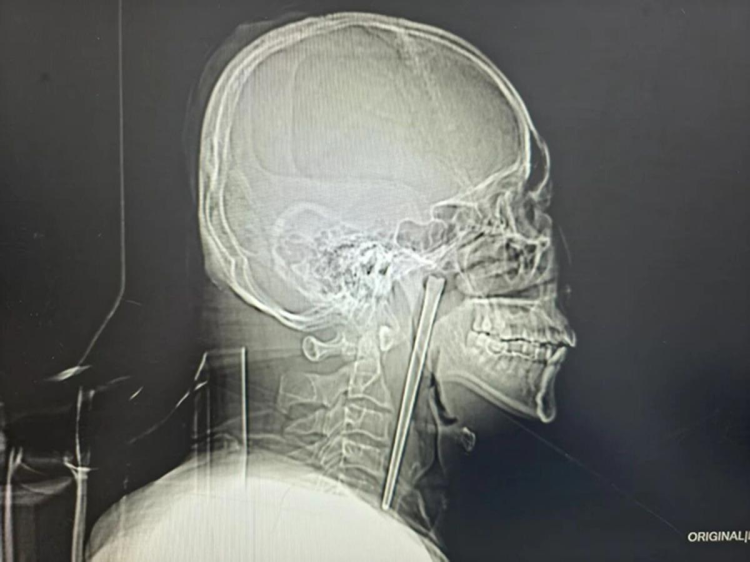

Doktorlar, Wang'ın boğazını incelediklerinde dokularda herhangi bir kanama veya iltihaplanma görmediler. Ancak çekilen röntgen filmi gerçeği tüm çıplaklığıyla ortaya koydu: Boğazın iç kısımlarına yerleşmiş, 12 santimetre uzunluğunda, metal bir şaft duruyordu. Çubuk, her an hayati damarlara zarar verebilecek veya doku hasarına yol açabilecek bir saatli bomba gibiydi.